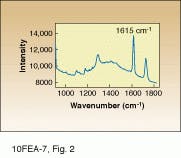

Raman scattering is ideal for this work because Dacron produces a reasonably intense Raman spectrum with cleanly resolved spectral peaks (see

Fig. 2). As a result, molecular-specific images can be obtained without the use of stains or dyes, even in such a complex biomatrix. In this study, the slide-mounted sections were illuminated using the 647.1-nm line of a Coherent krypton-ion laser. Raman-scattered light was collected by a microscope coupled to a 16-bit, red-enhanced, back-thinned CCD with 512 ¥ 512 pixels from Princeton Instruments (Trenton, NJ). Rapid wavelength filtering of the detected light was facilitated by use of an AOTF integrated within the Raman microscope.

Samples were imaged containing Dacron that had migrated through the breast tissue, forming local aggregates and microstructures (see Fig. 3 and cover). Conventional optical microscopy could not unequivocally determine which of the observed structures were due to Dacron inclusions. One image in Fig. 3 is a bright-field image of the breast-tissue cross section. The other, a Raman image, was taken at 1615 cm-1, which is specific to Dacron. The presence of Dacron was confirmed by using the Raman microscope to take Raman microspectra of these structures at each of the several thousand pixels contained in the chemical image data set.

FIGURE 2. Raman spectrum of a Dacron

inclusion in biopsied breast tissue cross section shows characteristic peak at 1615 cm-1 that

can be identified in the imaging process.

FIGURE 3. In Raman pathology studies of Dacron in human breast tissue, bright-field image taken through a microscope reveals aggregates (A), while Raman image (taken at 1615 cm-1 ) shows inclusions as bright structures (B).